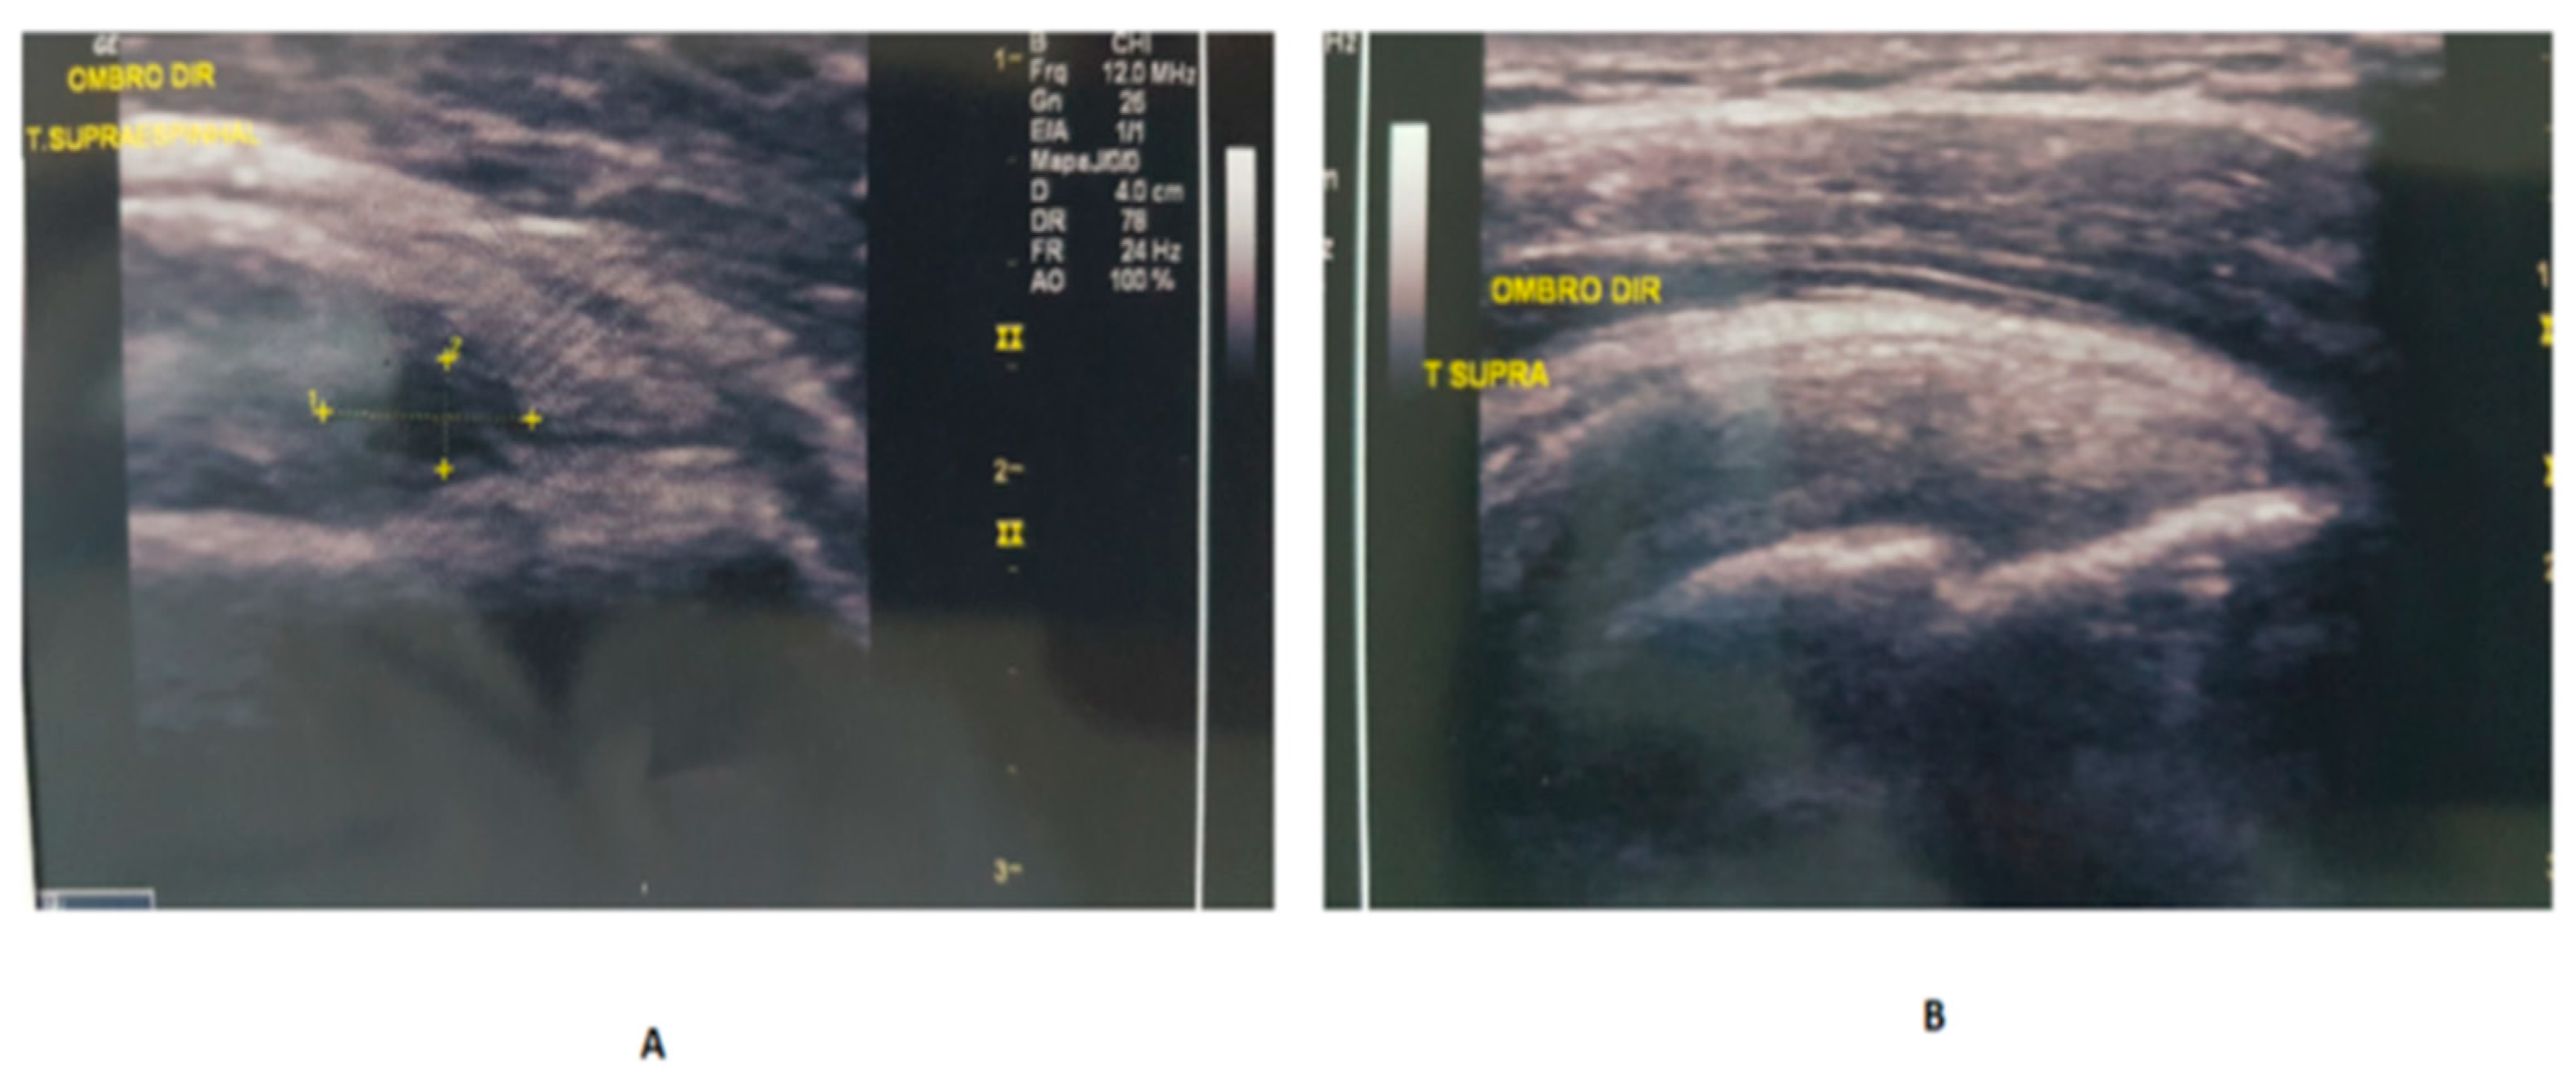

2.3.1. Evaluation by US